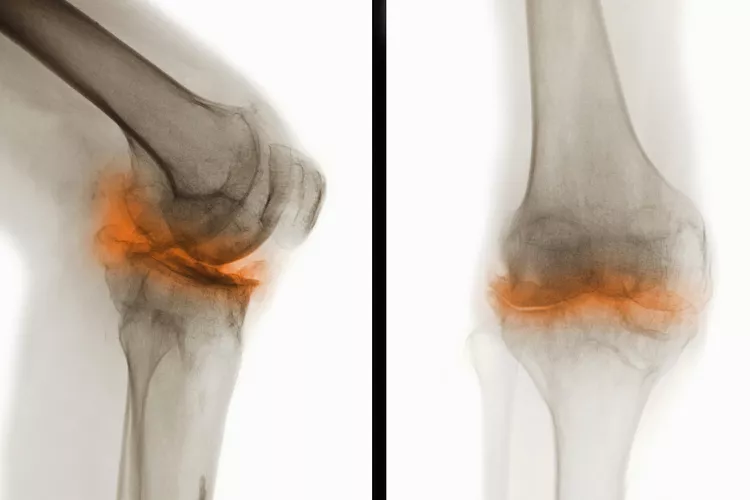

骨關節炎(Osteoarthritis, OA),一種常見的慢性關節疾病,主要特征是關節軟骨退化和關節邊緣骨質增生。隨著病情進展,骨關節炎不僅會導致關節疼痛和功能受限,還可能引發一系列并發癥,影響患者的整體健康和生活質量。

在骨關節炎(OA) 中,覆蓋骨頭末端并幫助骨頭相互滑動的光滑軟骨會逐漸磨損。這會導致骨頭相互摩擦和磨擦。

關節損傷

可能的問題包括:

- 脊柱神經受到擠壓(后天性脊椎滑脫或脊椎狹窄)

- 關節感染,但這種情況很少見

- 關節周圍的肌腱和韌帶變薄或撕裂,導致關節不穩定

- 軟骨溶解癥,軟骨突然完全破裂,導致關節內組織松散

- 應力性骨折,由于反復的壓力而緩慢地在骨頭上形成細微裂縫

- 貝克囊腫是膝蓋后面的軟性充滿液體的腫塊。它們大多無痛,但會壓迫血管導致腿部腫脹,或破裂并引起疼痛